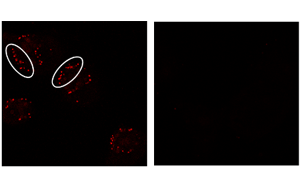

密歇根大學(xué)Rogel癌癥中心的研究人員發(fā)現(xiàn)了一些癌癥對(duì)免疫治療沒有反應(yīng)的關(guān)鍵原因:腫瘤微環(huán)境中的代謝物轉(zhuǎn)運(yùn)體阻斷了免疫反應(yīng)不可或缺的一種關(guān)鍵類型的腫瘤細(xì)胞死亡。